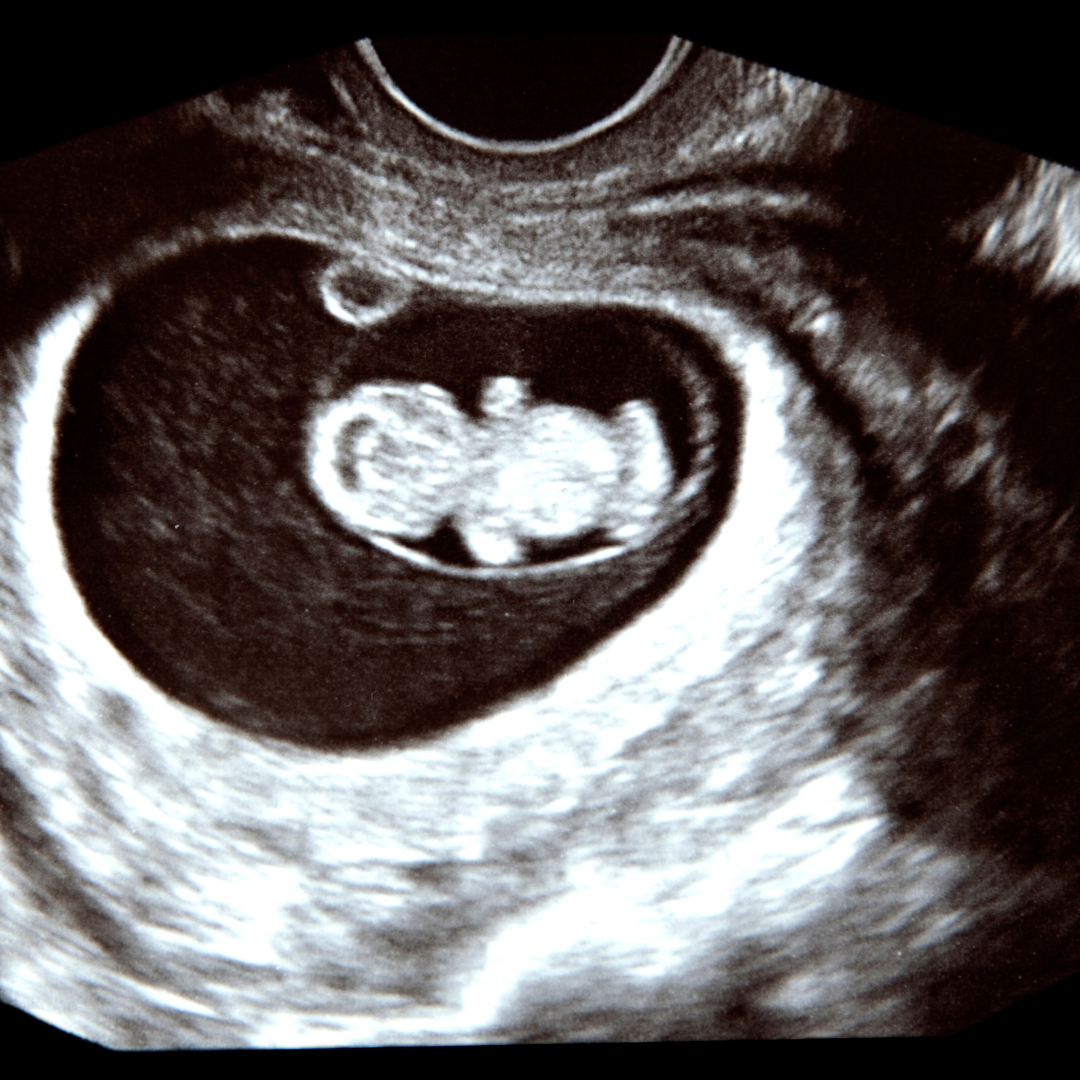

Understanding the early signs of pregnancy is an important step in taking care of yourself and your growing baby. If you're noticing some of these signs and think you may be pregnant, it’s a good idea to take a pregnancy test or schedule an early pregnancy scan West Yorkshire. At Miracle Inside, we're here to help you navigate this exciting and sometimes overwhelming time with expert guidance and compassionate care.

If you're in West Yorkshire and want to confirm your pregnancy early, contact Miracle Inside today to book your scan. Let's take